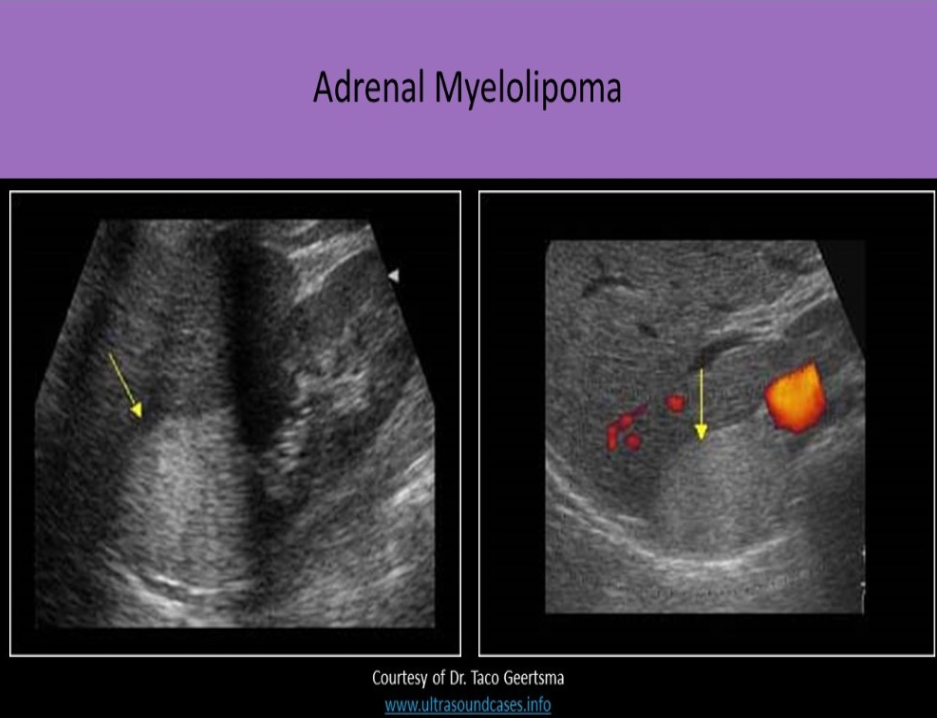

Which of the following is not an expected finding with adrenal myelolipoma?

B. comet tail artifacts

Adrenal myelolipomas are composed of fatty and bony elements that cause the mass to be echogenic on ultrasound evaluation. Fatty tissue causes increased attenuation of the ultrasound beam. Diaphragm disruption due to propagation speed artifact may be identified. The decrease in the speed of sound in fatty tissue can cause the portion of the diaphragm that is posterior to the mass to be placed more posterior on the image so the diaphragm looks "broken". Comet tail artifacts are caused by repetitive reflections at a media boundary between very different tissues. They are usually associated with tissue/gas or tissue/fluid interfaces.

Which of the following correctly describes myelolipoma?

D. adrenal tumor that is composed of fat and bony elements

An adrenal myelolipoma usually originates in the adrenal cortex and is composed of fat and bony elements. The mass is hyperechoic and causes varied levels of sound attenuation, posterior shadowing and propagation speed artifact. Large masses can be associated with acute retroperitoneal hemorrhage. These masses can be associated with Cushing syndrome, Conn syndrome and adrenal hyperplasia.